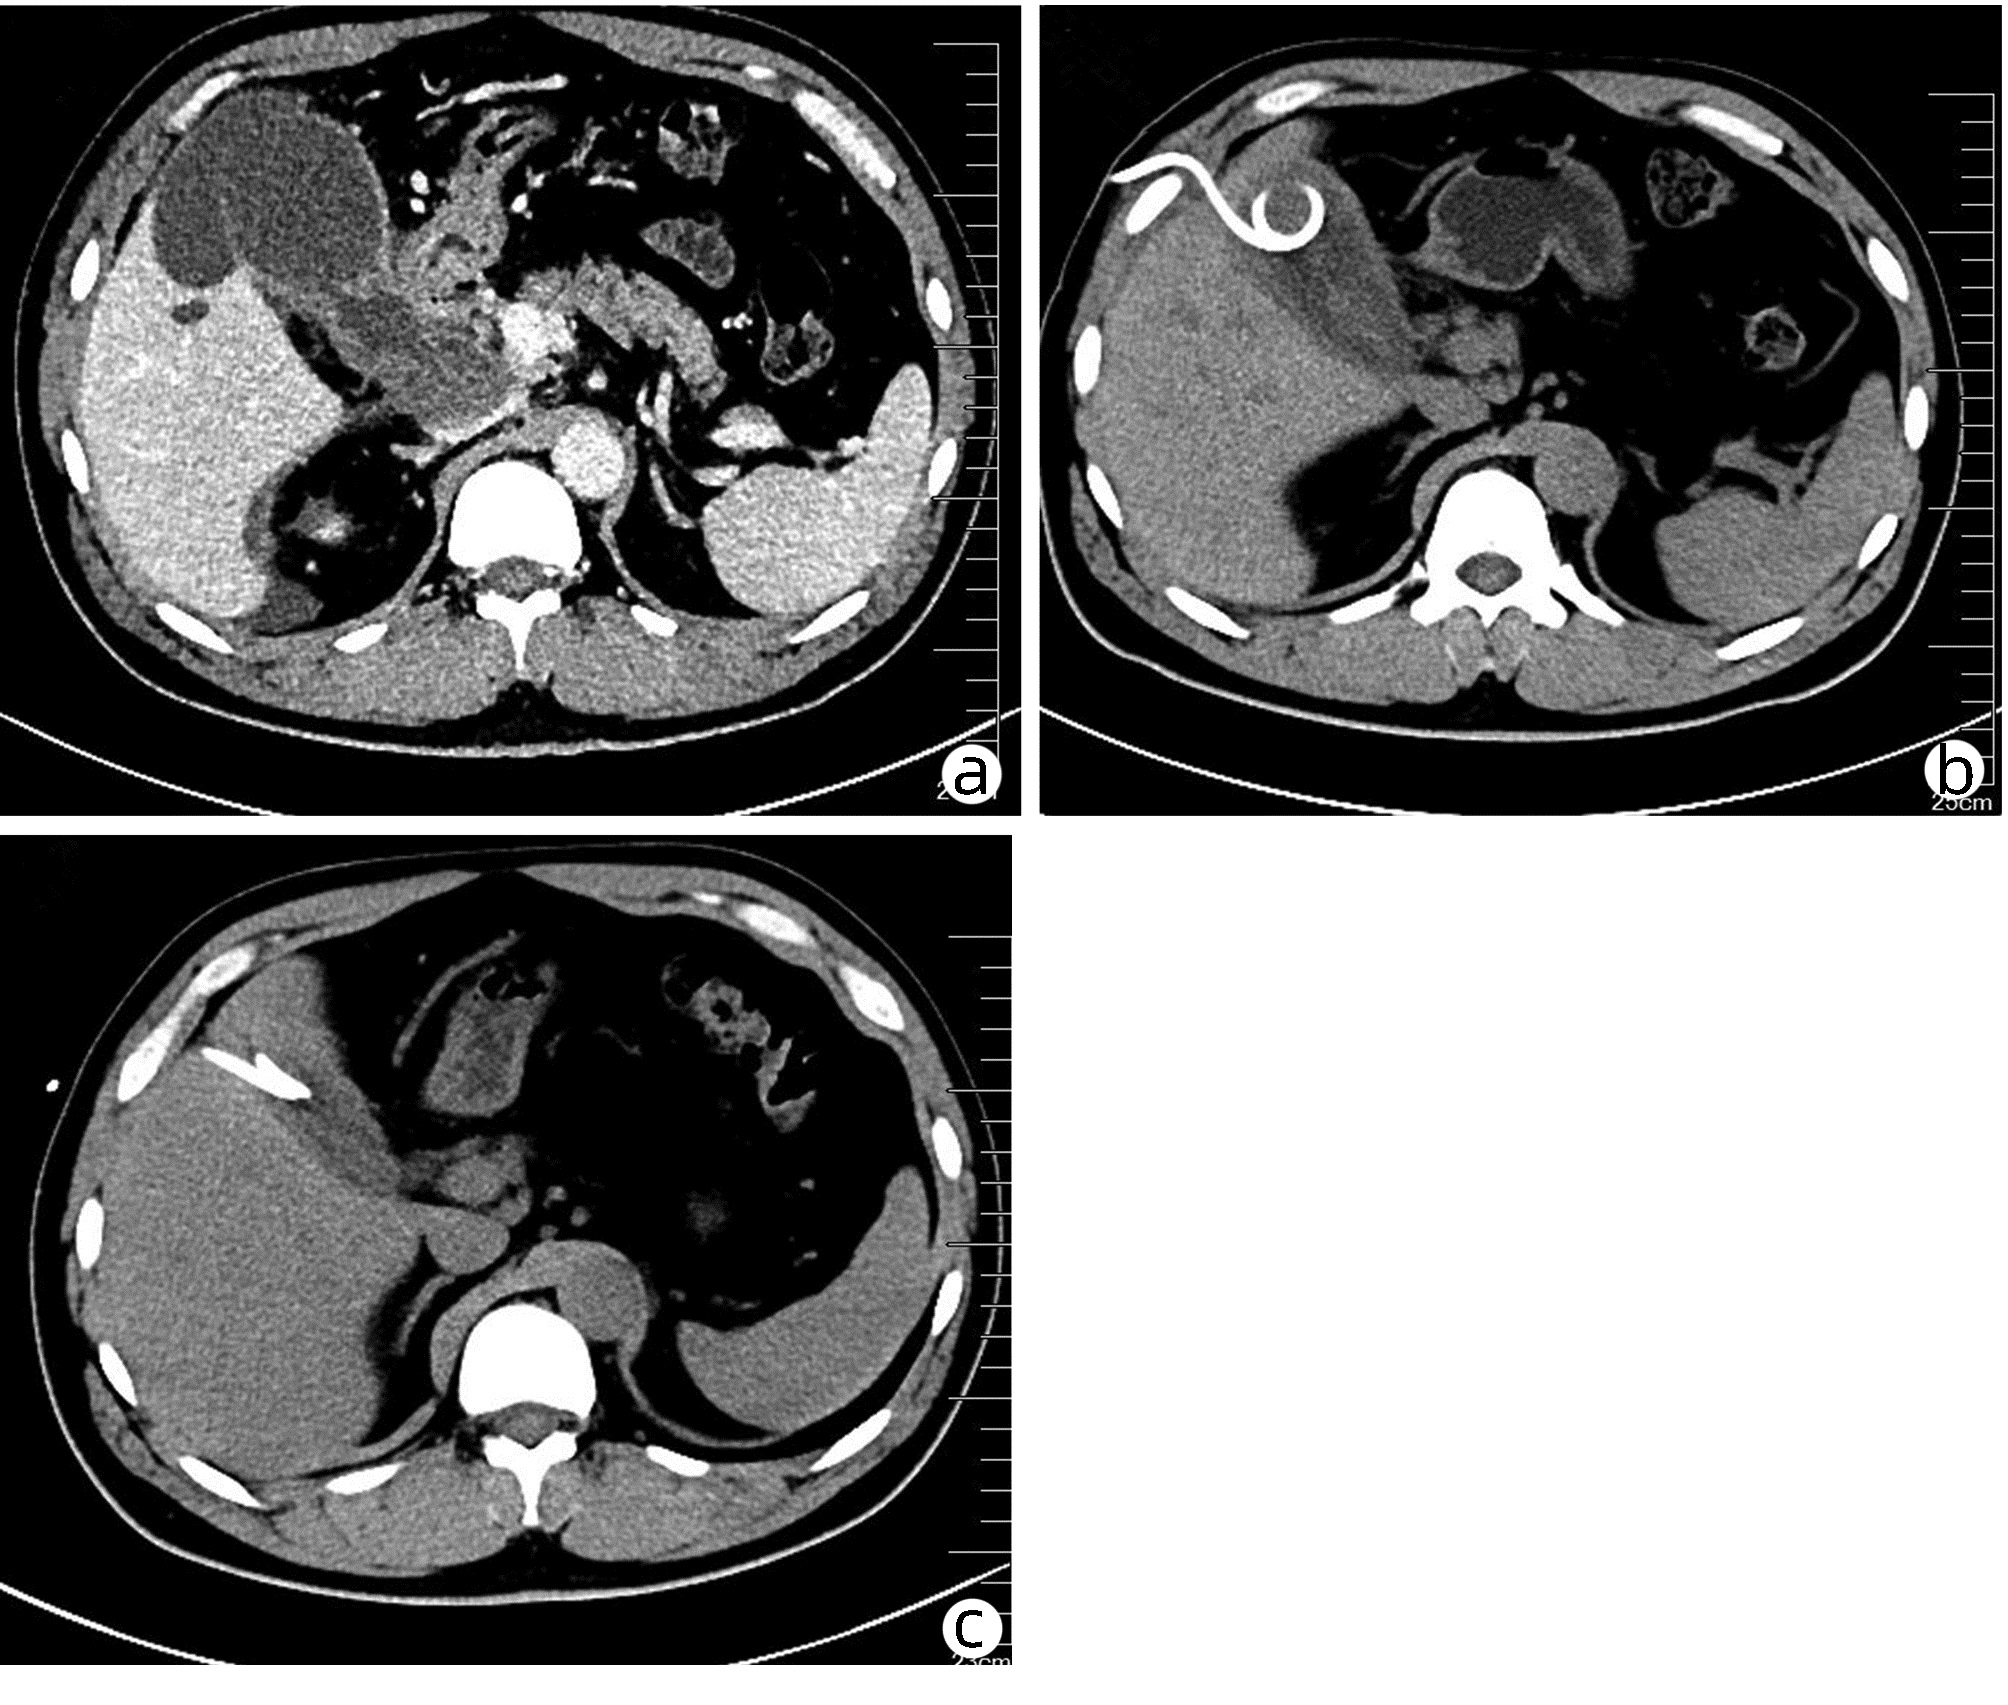

Liver abscess caused by type II gallbladder perforation: A report of 3 cases and literature review

Shaoxiong REN, Ze LIANG, Jingzhao HAN, Hongfang TUO, Yanhui PENG

2022, 38(4): 894-897. DOI: 10.3969/j.issn.1001-5256.2022.04.031

Abstract(1105) HTML (269) PDF (2784KB)(47)

Abstract: